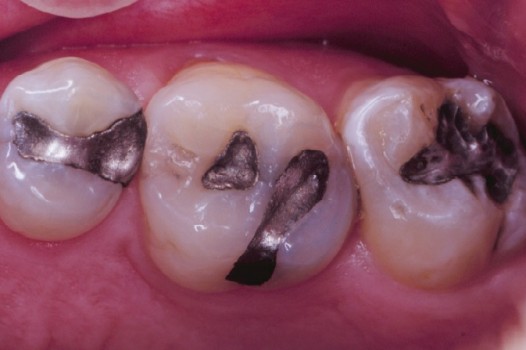

Traditional amalgam (mercury) fillings have been used for over a century, but concerns about health risks, tooth fractures, and long-term decay have led many dentists to adopt modern alternatives. Today, metal-free restorations offer healthier, stronger, and more natural-looking results.

Using advanced resins, ceramics, and state-of-the-art bonding techniques, Dr. Klim can restore teeth with precision, preserving healthy tooth structure while preventing fractures, bacterial invasion, and future toothaches.